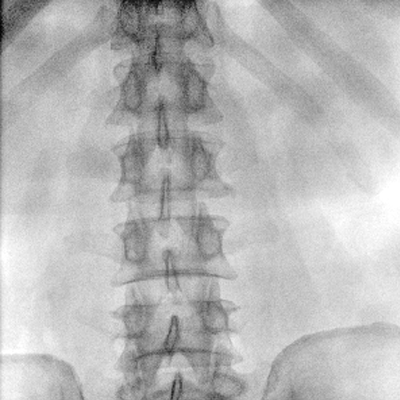

大尺寸動態(tài)平板探測器,高DQE、低噪聲、圖像清晰。采用多分辨率圖像增強處理技術(shù),不同部位不同圖像處理算法,滿足客戶多樣化的需求。

多角度自由旋轉(zhuǎn),滿足患者復(fù)雜擺位需求。